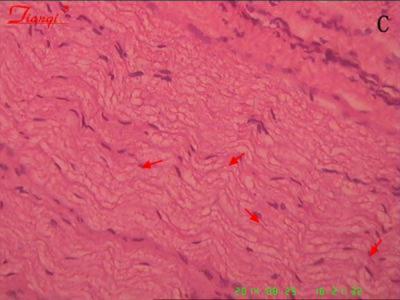

人羊膜上皮细胞移植修复损伤臂丛神经:具

以牵拉神经根的方法制备C6臂丛神经损伤动物模型,造模后即刻用微量注射器接无菌玻...